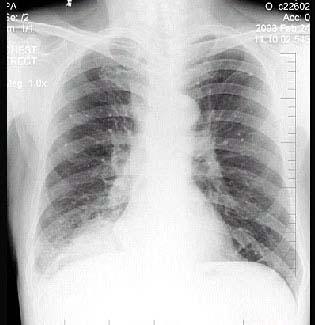

男性,62岁,咳嗽、胸痛1月,X线检查如图,最佳的诊断是 ( )A.右下肺炎症B.右下肺不张C.右肺癌D.右肺转移瘤E.右胸腔积液

问题 男性,62岁,咳嗽、胸痛1月,X线检查如图,最佳的诊断是 ( )

选项 A.右下肺炎症 B.右下肺不张 C.右肺癌 D.右肺转移瘤 E.右胸腔积液

答案 C